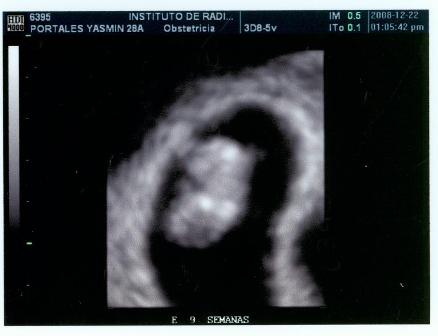

Fotos del 22 Dc 2008:

Informe:

Embrión correspondiente a 9 s cumplidas de embarazo y con FC (frecuencia cardiaca, supongo) de 162 LPM.

Saco gestacional bien conformado y localizado en fondo uterino.

Estructura uniforme de útero con cuello cerrado, ausencia de signos de sangrado gestacional.